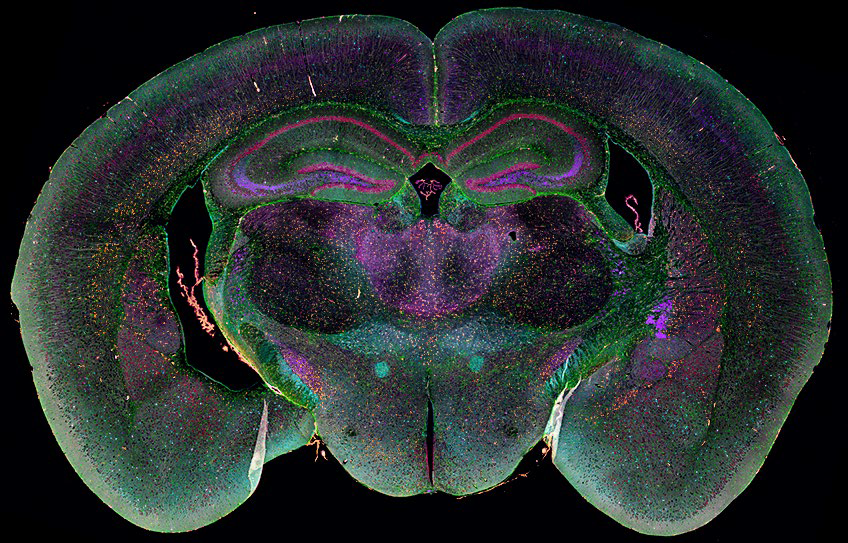

EVOS S1000也可以用于神经元细胞的空间组学研究。使用EVOS S1000对正常小鼠脑组织进行分析,以识别单细胞靶标表达和神经元细胞亚群的特定定位。这里分析了3.5 mm²区域内的4763个细胞,识别了特定区域的细胞定位。

图4 正常小鼠脑组织